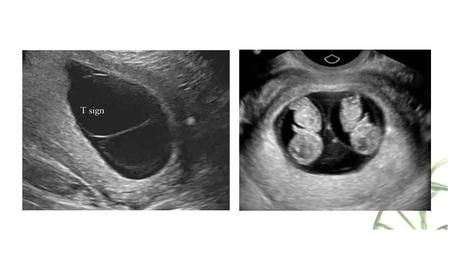

Kết quả siêu âm cho thấy song thai có chung một bánh rau, hai buồng ối từ tuần thai thứ 8. Sau khi hội chẩn, siêu âm và chọc ối phát hiện thai A phù thai, giới tính nữ, kiểu gene nữ Turner(45,X).

Thai B bình thường về mặt hình thái, giới tính trên siêu âm là nam, kiểu gene nam (46,XY). Các xét nghiệm di truyền chuyên sâu khác cũng đã được thực hiện và chứng minh rằng 2 thai này chung 1 trứng nhưng có kiểu gene khác nhau.